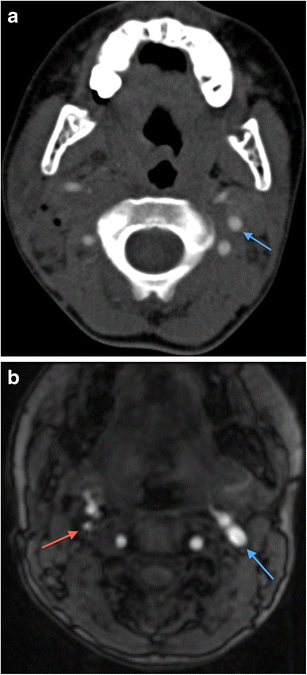

a Axial non-contrast CT face image in a 19-year-old male victim of a shotgun injury to the orbito-facial region. Multiple shotgun pellets are identified in the malar soft tissues, nasal fossae, maxillary sinuses, nasopharynx and masticator space, particularly on the right at this axial level. Fracture fragmentation of the right maxillary sinus, malar and retroantral haematoma and antral haemorrhagic fluid are present. The involvement of the nasal, nasopharyngeal and oral (the latter not shown) airway raises potential for distal migration of pellets (as well as of in-driven tissue fragments) through the upper aerodigestive tract into the lower respiratory tract and gastrointestinal tract. b Plain chest radiograph in the same patient as in 13a performed during trauma survey on admission demonstrates distal migration of a shotgun pellet (blue arrow) into the mid-oesophagus (confirmed on CT chest assessment [not shown]). The patient is intubated. c Axial image of a contrast-enhanced CT thorax of the same patient as in a and b, performed 12 h later also confirms aspiration of a shotgun pellet (blue arrow) associated with distal subsegmental left lower lobe atelectasis (blue arrowhead). There had also been further distal intra-oesophageal migration of the mid-oesophageal shotgun pellet (image not shown)